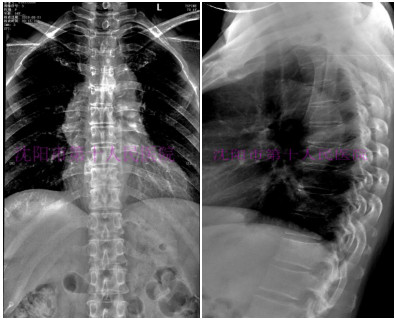

典型病2:

患者女,54岁,背部伴双季肋部疼痛3个月,出现低热,盗汗,乏力症状未在意,后疼痛逐渐加重,影响正常生活,进行穿刺活检后,明确诊断,本科给予改良肋横突手术治疗,治疗后患者自诉“太神奇了,又能从病床上起来生活工作了”

术前DR提示:胸10-11椎体间隙变窄